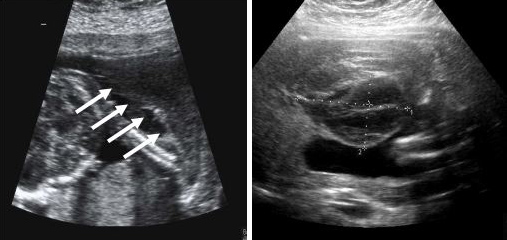

Most of the blood clots that turn up on sonograms during the first trimester are what doctors call subchorionic hematomas. Hematoma doesn’t necessarily mean that the pregnancy will eventually fail. Some treatments for vaginal bleeding during pregnancy can include: